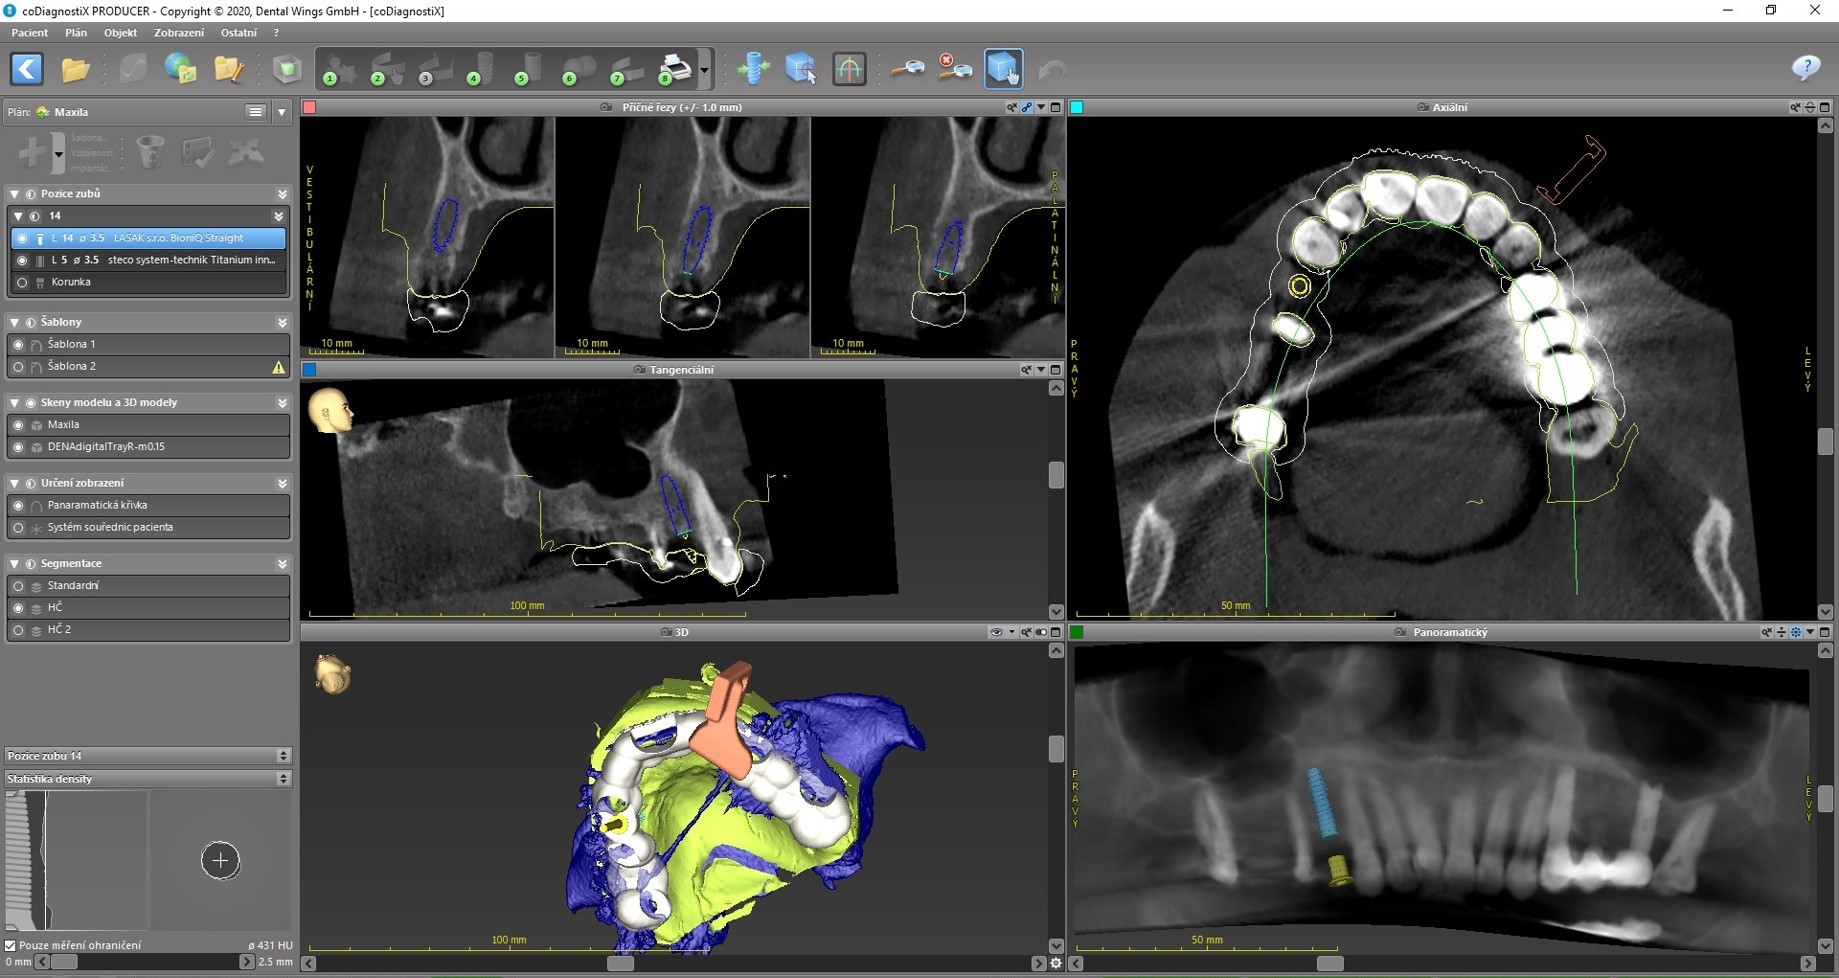

Ein CBCT-Scan des Oberkiefers wurde angefertigt und dieser anschließend mit dem modellgetreuen Scan mithilfe der Software coDiagnostiX zusammengefügt. Es wurden eine festsitzende metallkeramische Zahnbrücke auf den Zähnen 17–15 und eine metallkeramische implantatgetragene verklebte Zahnkrone für Regio 14 geplant und entworfen.

Aufgrund der Messung des Knochenangebots wurde ein 14 mm langes Implantat BioniQ® Straight mit Ø 3,5 mm für Regio 14 eingeplant.

Um die Implantatsetzung so genau wie möglich zu gestalten (angesichts des begrenzten Knochenangebots sowie der Implantatlänge von 14 mm) und um die nahestehende Wurzel des Nachbarzahns zu umgehen, wurde eine kombinierte Operationsschablone entworfen.